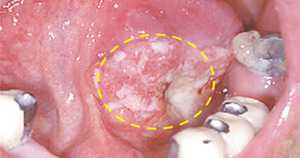

초기에는 단순한 입안 염증이나 구내염으로 착각하기 쉬워요.

하지만 2주 이상 낫지 않거나, 점점 커지는 궤양·혹·붓기가 있다면 구강암을 의심해야 합니다.

- 입안에 하얗거나 붉은 반점이 생기고 잘 낫지 않음

- 혀, 잇몸, 볼 안쪽에 덩어리나 혹이 만져짐

- 시진(눈으로 관찰) : 궤양, 혹, 변색 부위를 직접 확인